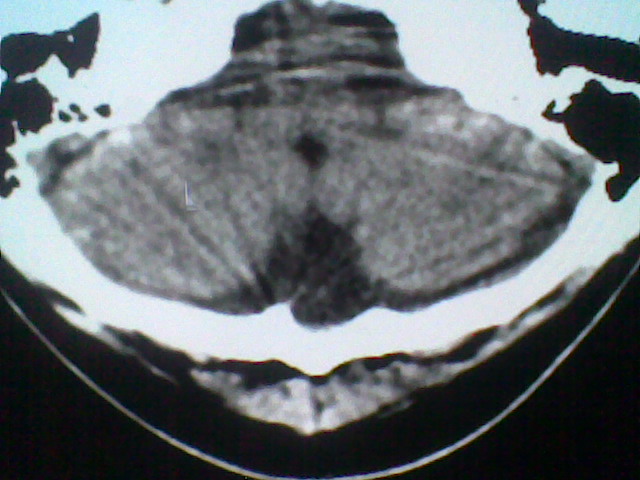

患者,男,头晕4天来诊,要求ct。

大枕大池合并蛛网膜囊肿。

支持 大枕大池合并蛛网膜囊肿。

考虑大枕大池合并蛛网膜囊肿。

考虑大枕在池

有没有dandy-walker综合征的可能?